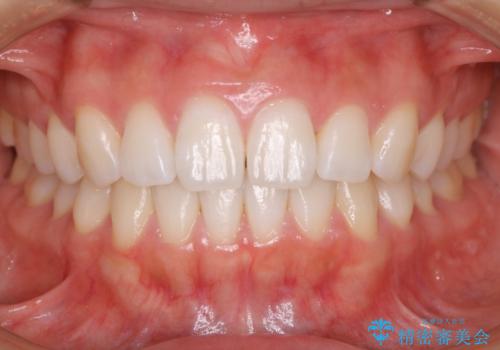

インビザライン矯正 前歯のすきっ歯を治したい